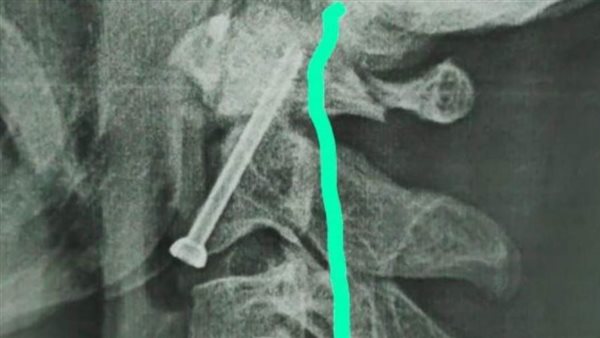

واوضح الدكتور حمدي سعد مدير المستشفى الجامعي انه بعد اجراء الفحوصات والاشاعات اللازمة للمريض تبين وجود كسر في الفقرة الثانية من العمود الفقري الرقبي، ويحتاج إلى جراحة عاجلة لتثبيت الفقرة العنقية، حيث كان هذا الكسر يشكل خطراً كبيراً على النخاع الشوكي وحياه المريض.

وذكر الدكتور عبدالرحمن الشيخ رئيس قسم جراحة العظام انه بعد دراسة الحالة في ضوء نتائج الفحوصات الطبية، تم اتخاذ كافة التدابير التحضيرية للعملية، لافتاً الي ان الفريق الطبي الذي إجري العملية الجراحية للمريض كان تحت اشراف الدكتور أحمد صالح أستاذ جراحة العظام والعمود الفقري، حيث تم تثبيت الكسر بنجاح، و بدأ المريض الحركة بحرية تامة بمفرده بدون اي وسائل مساعدة.